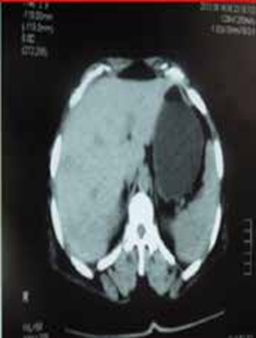

La tomodensitométrie abdominale avec opacification confirmait cette cholécystite avec un foie hétérogène, siège de multiples microlésions arrondies hypodenses, rehaussées légèrement après injection de produit de contraste (Figures 3, 4).